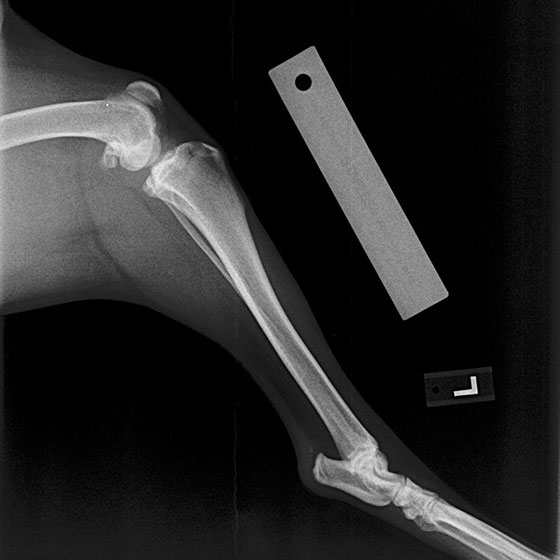

• Diagnosis: Our veterinarians use a combination of physical examinations, palpation tests like the cranial drawer test, and often radiographs to confirm CCL tears. Early diagnosis can prevent further damage to the joint.

• Surgical Repair: The most effective treatment for CCL tears, especially in active or large dogs, includes various techniques like extracapsular stabilization, TPLO (Tibial Plateau Leveling Osteotomy), or TTA (Tibial Tuberosity Advancement). These surgeries aim to stabilize the knee joint and reduce arthritis progression. Generally speaking, TPLO is superior to TTA, which is superior to extracapsular technique but our doctors will help you decide what is optimal for you and your pet.